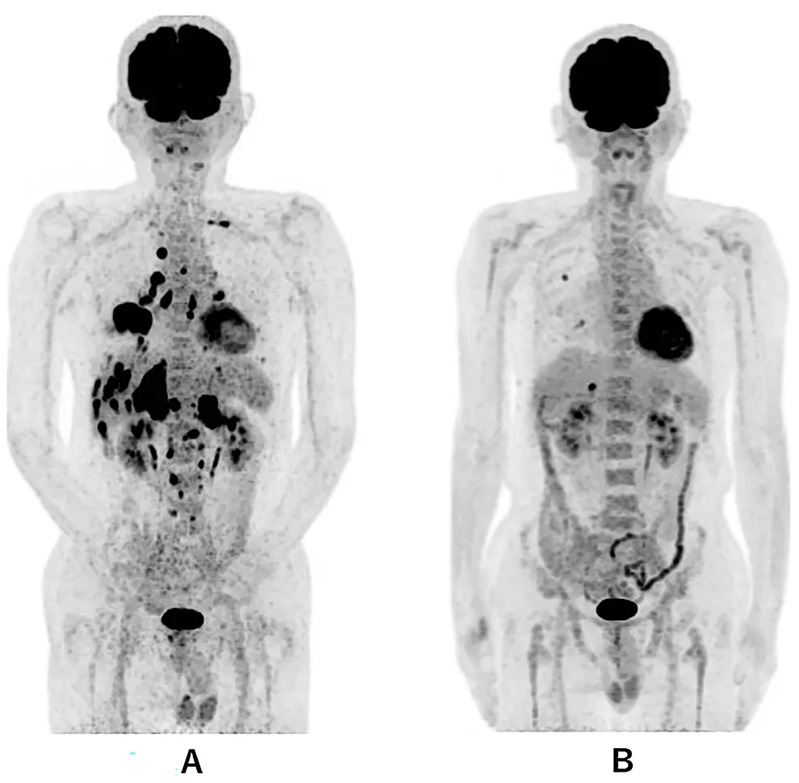

2023 年 10 月,国际期刊《Cureus》发表了一则 WT1-DC 疫苗治疗晚期肺癌的案例:69 岁男性患者确诊 “右肺中叶 IV 期鳞状细胞癌”,伴随肾上腺、肝、骨等多处转移,无法手术和放疗。医生采用 WT1-DC 疫苗联合化疗方案治疗后:

1、患者的免疫指标持续改善(淋巴细胞比例上升、炎症指标下降);

2、第 338 天胸部 CT 显示,原发和复发病灶缩小;

3、第 479 天 PET-CT 仅残留两个小转移灶,截至报道时,患者无进展生存期已超 577 天,生活正常。